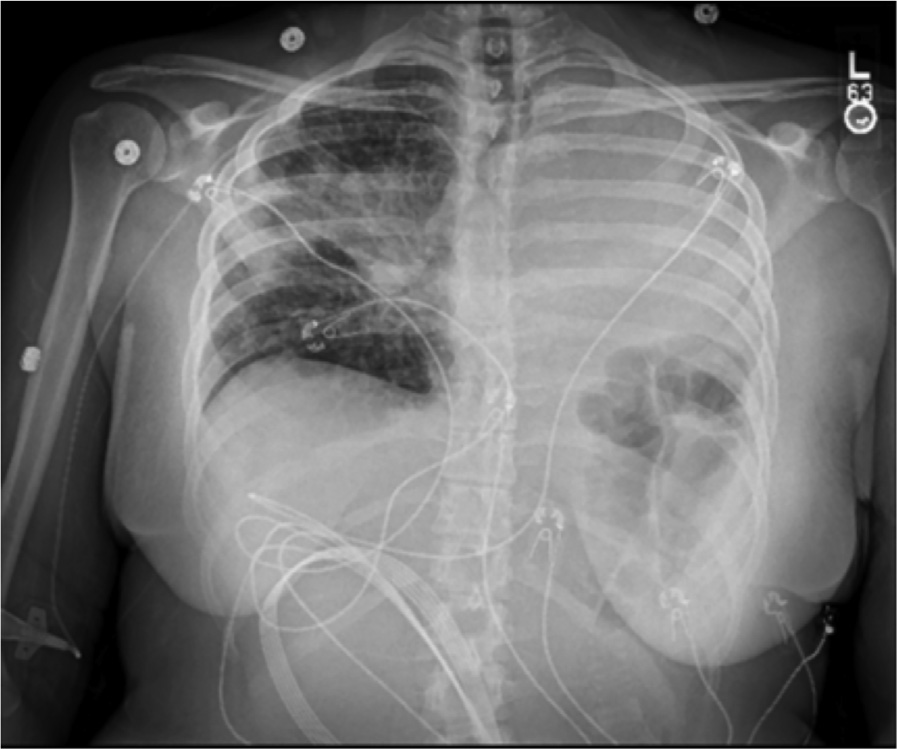

胸片及CT胸部扫描显示右上肺阴影明显增大,下颈部及胸部广泛淋巴结病变,继发于淋巴结病变的左主干支气管完全闭塞,新发完全性左肺不张

伴中度胸腔积液

(图1、2)。

图1 胸片显示右肺门周围及肺上叶病变,左半胸完全浑浊,左半膈抬高。

图2 胸部CT扫描显示右上肺阴影,转移性淋巴结病变,左主支气管闭塞,左肺实变/肺不张。